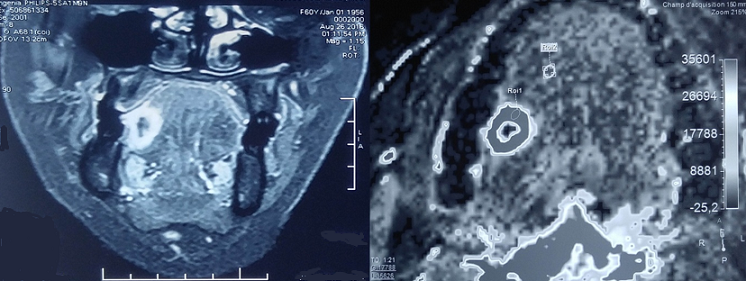

Le granulome de la cavité buccale constitue la circonstance de découverte de plusieurs pathologies comme la sarcoïdose, la maladie de Crohn, la tuberculose, la syphilis et les tumeurs malignes. Son origine idiopathique est classique dans le syndrome de Melkerson Rosenthal. A ce propos, nous rapportons l'observation originale d'un granulome idiopathique de la langue non secondaire à un syndrome de Melkerson Rosenthal et faisant partie des tumeurs bénignes de la cavité buccale. Il s'agit d'une patiente âgée de 60 ans sans antécédents pathologiques particuliers qui a présenté un mois avant son admission une gêne au cours de la mastication secondaire à une tuméfaction au niveau du bord libre de la langue. A l'examen, elle avait une excroissance au niveau du bord latéral droit de la langue faisant 15mm de grand axe. Sa langue n'était pas plicaturée et il n'y avait pas d'adénopathies cervicales. Le reste de l'examen somatique était sans particularités. L'IRM de la cavité buccale avait montré une lésion tissulaire nécrosée du bord libre droit de la langue mobile, d'allure suspecte mesurant 15x12x19mm sans signes d'extension au pédicule lingual homolatéral ni au plancher buccal et sans adénomégalies cervicale. La biopsie de la lésion de la langue avait montré des granulomes épithélioïdes et giganto-cellulaires sans nécrose caséeuse et sans signes histologiques de malignité. Sur le plan biologique, il n'y avait pas de syndrome inflammatoire, ni de leucopénie ou de lymphopénie. Le bilan étiologique à la recherche d'une étiologie sous-jacente était négatif: sérologie syphilis, bilan phosphocalcique, dosage de l'enzyme de conversion de l'angiotensine, intradermo réaction à la tuberculine, radiographie du thorax, scanner thoraco-abdomino pelvien et examen ophtalmologique. Finalement, le diagnostic de granulome idiopathique a été retenu devant l'absence d'arguments en faveur de son caractère secondaire.